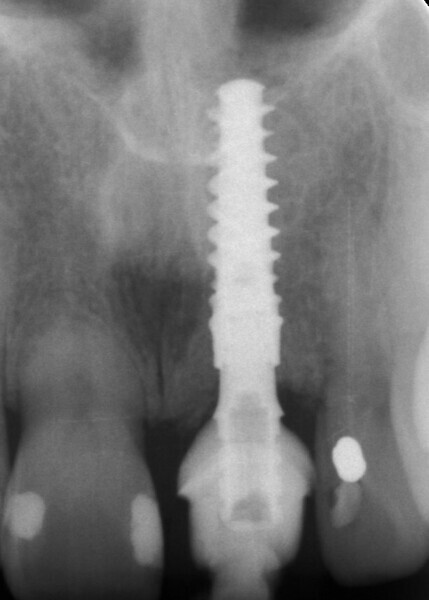

Fig. 3: Pre-op periapical radiograph.